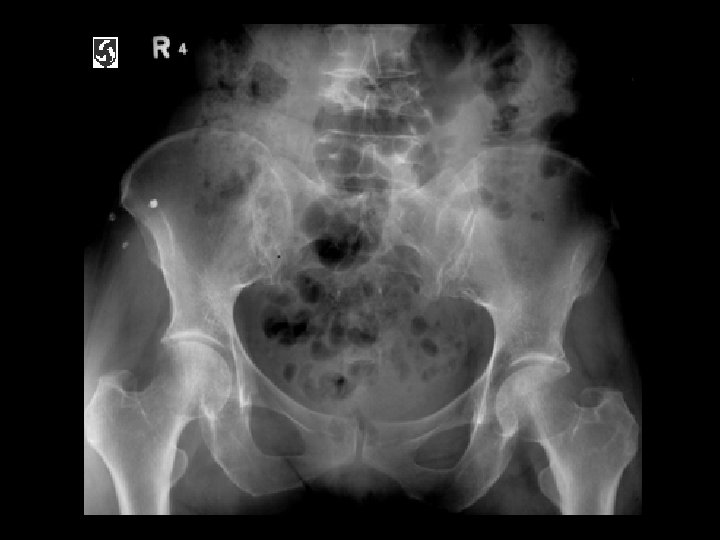

Ankylosing Spondylitis • Findings: – fused SI joints – right hip erosions – lumbar syndesmophytes • Sero-negative chronic inflammatory disease • Starts in the low back and progesses upward • ddx (sacroilitis) – bilateral • ank spond • IBD – unilateral • Reiter’s • psoriasis